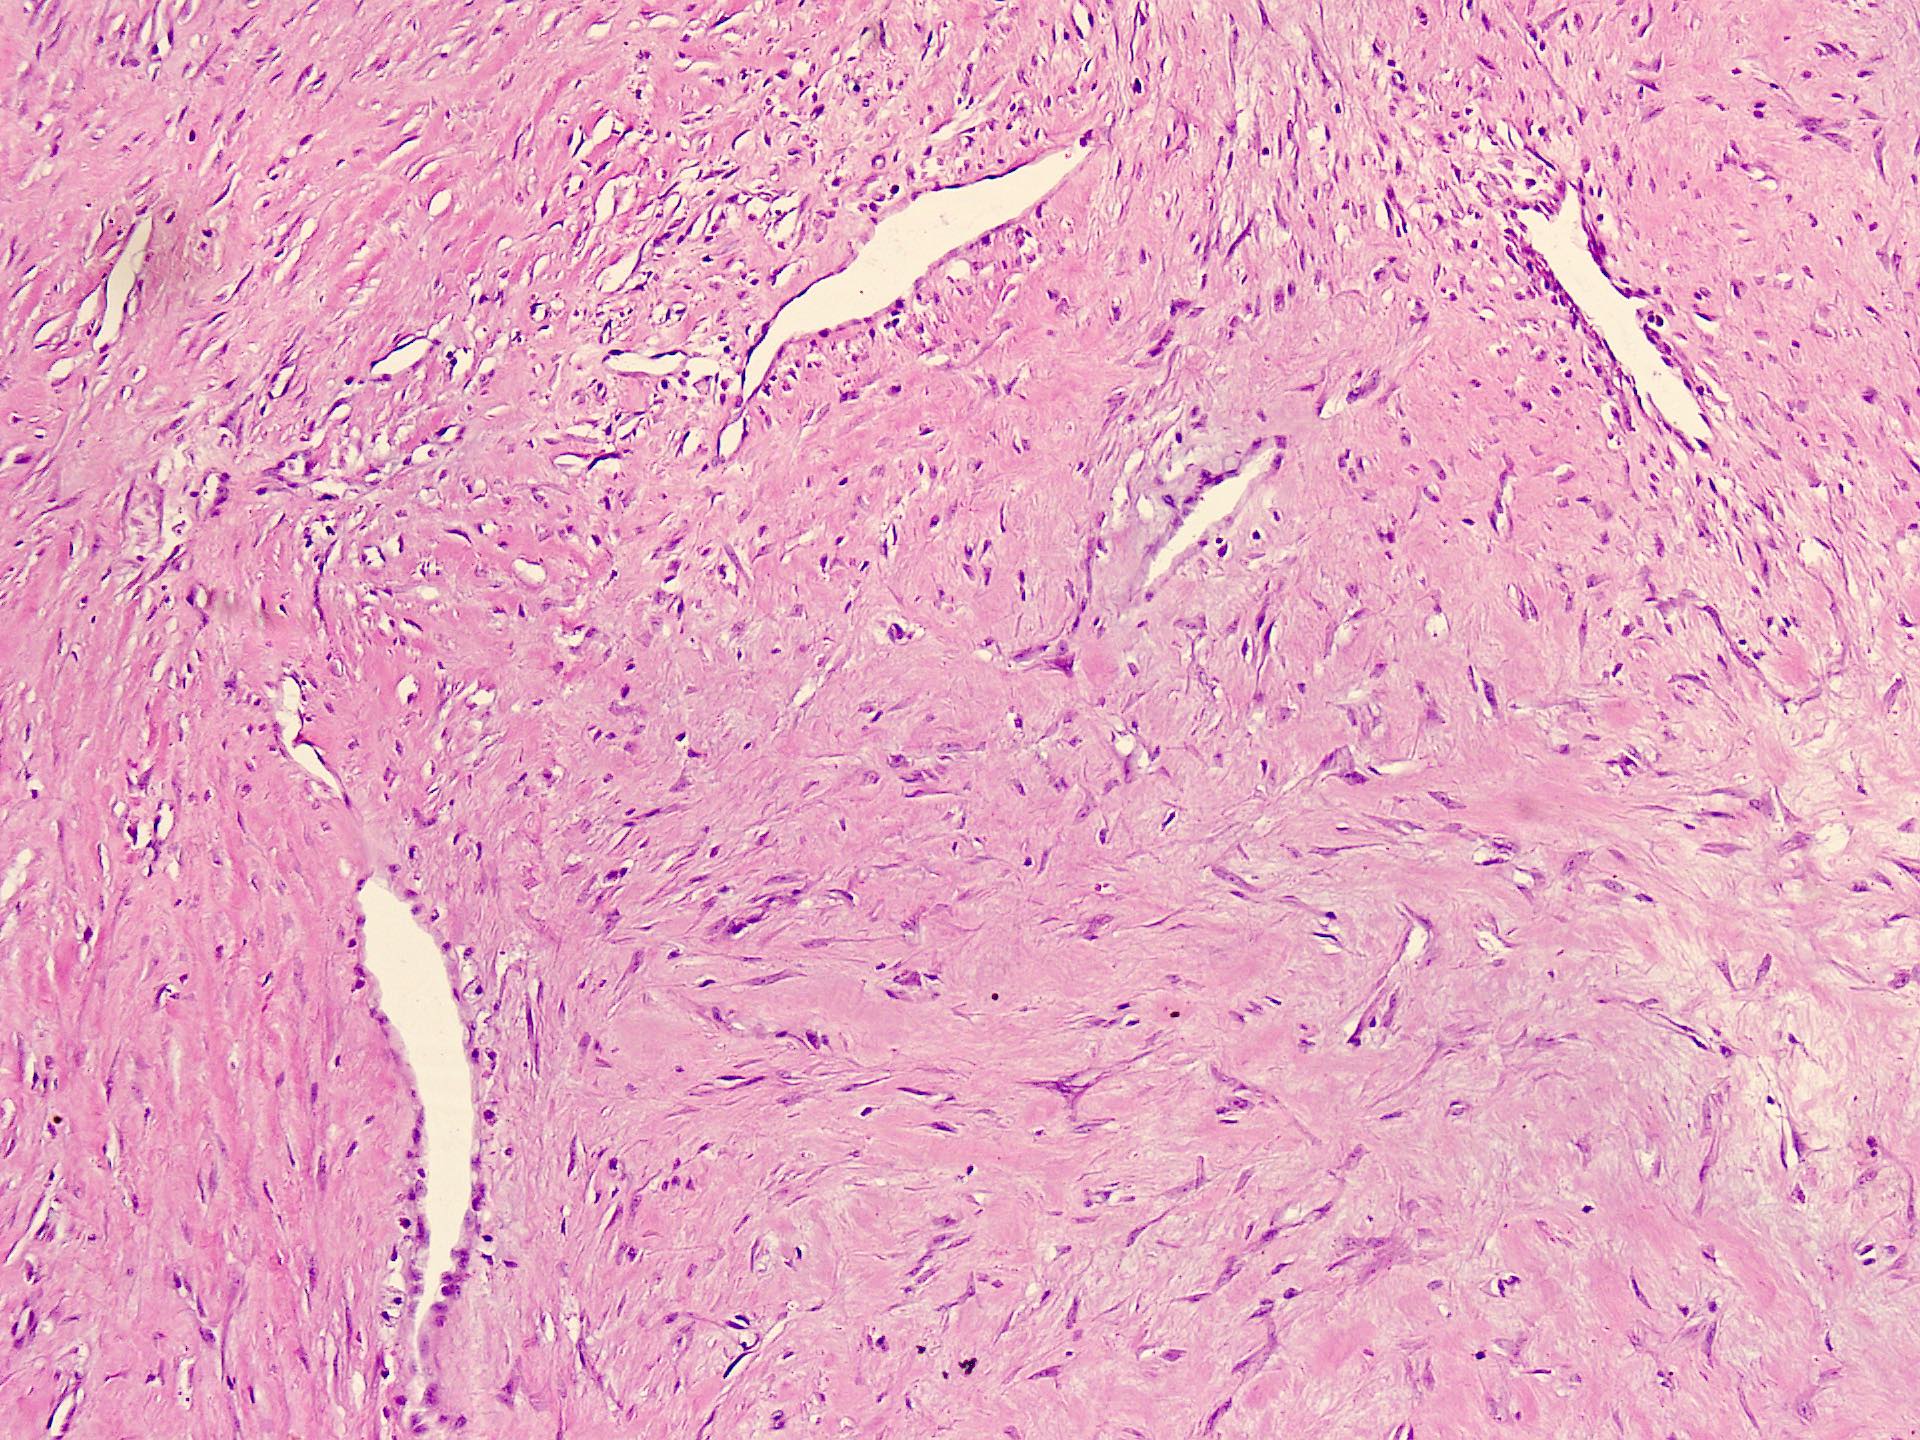

Microscopic (histologic) description

- Well circumscribed tumor of variable cellularity

- Cellularity mostly higher at tumor edges

- Bland spindle cells in a collagenous background

- Tumor has characteristic thin walled slit-like vessels

- Degenerative changes like myxoid / cystic change, osseous / chondroid metaplasia can be seen

- Bizarre pleomorphic cells can also be present

- Mitotically inactive

- Necrosis not present

- Cellular variant of fibroma of tendon sheath also exists; it overlaps morphologically with nodular fasciitis and fibrous histiocytoma (Cancer 1979;44:1945)

Microscopic (histologic) images

Contributed by Nasir Ud Din, M.B.B.S.

- Comment: Histology showed a well circumscribed, variably cellular lesion composed of bland spindle cells having regular nuclei arranged in sheets and fascicles. Thin walled vessels are present. The background is collagenous.

A 32 year old man has had painless swelling in the palm of his hand for 6 months. It was excised and the histology is shown in the above image. What is the most likely diagnosis?